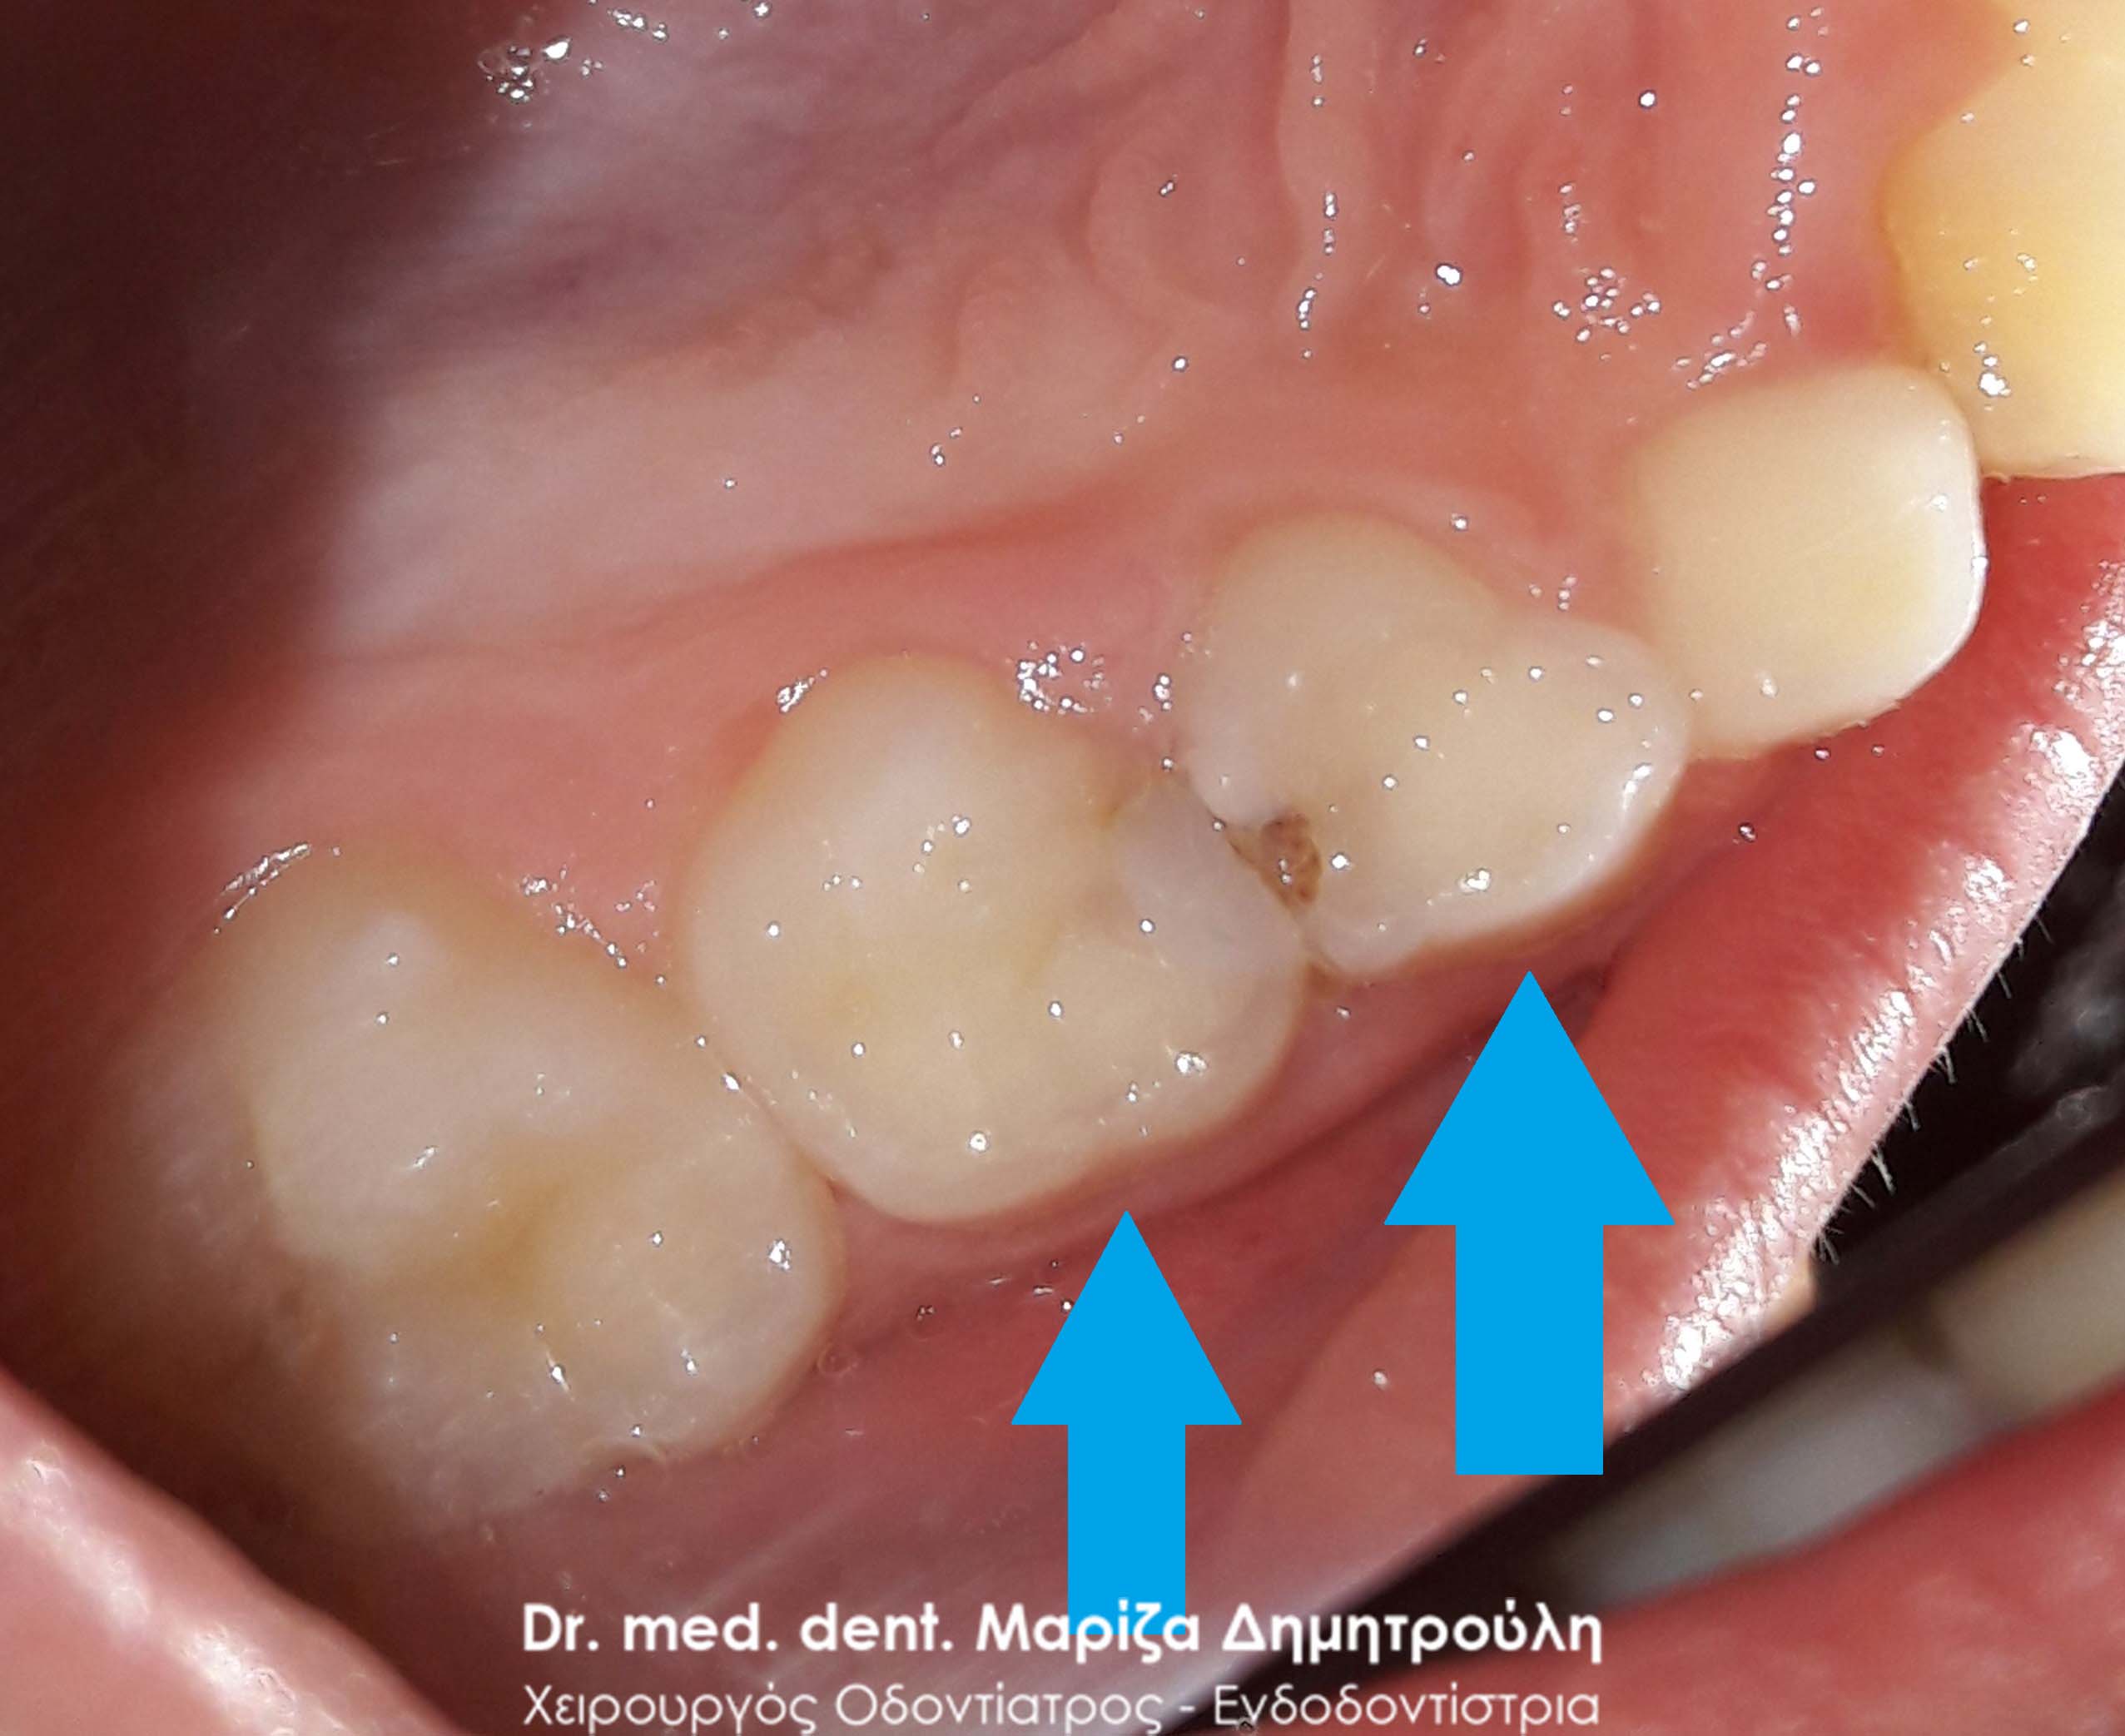

Ο ασθενής παραπονιέται για πόνο κατά τη μάσηση στη δεξιά πλευρά της άνω γνάθου. Η κλινική εξέταση αποκάλυψε δύο μικρές τερηδονικές κοιλότητες, οι οποίες αποκαταστάθηκαν με λευκό σφράγισμα ρητίνης.

ΠΡΙΝ

ΜΕΤΑ